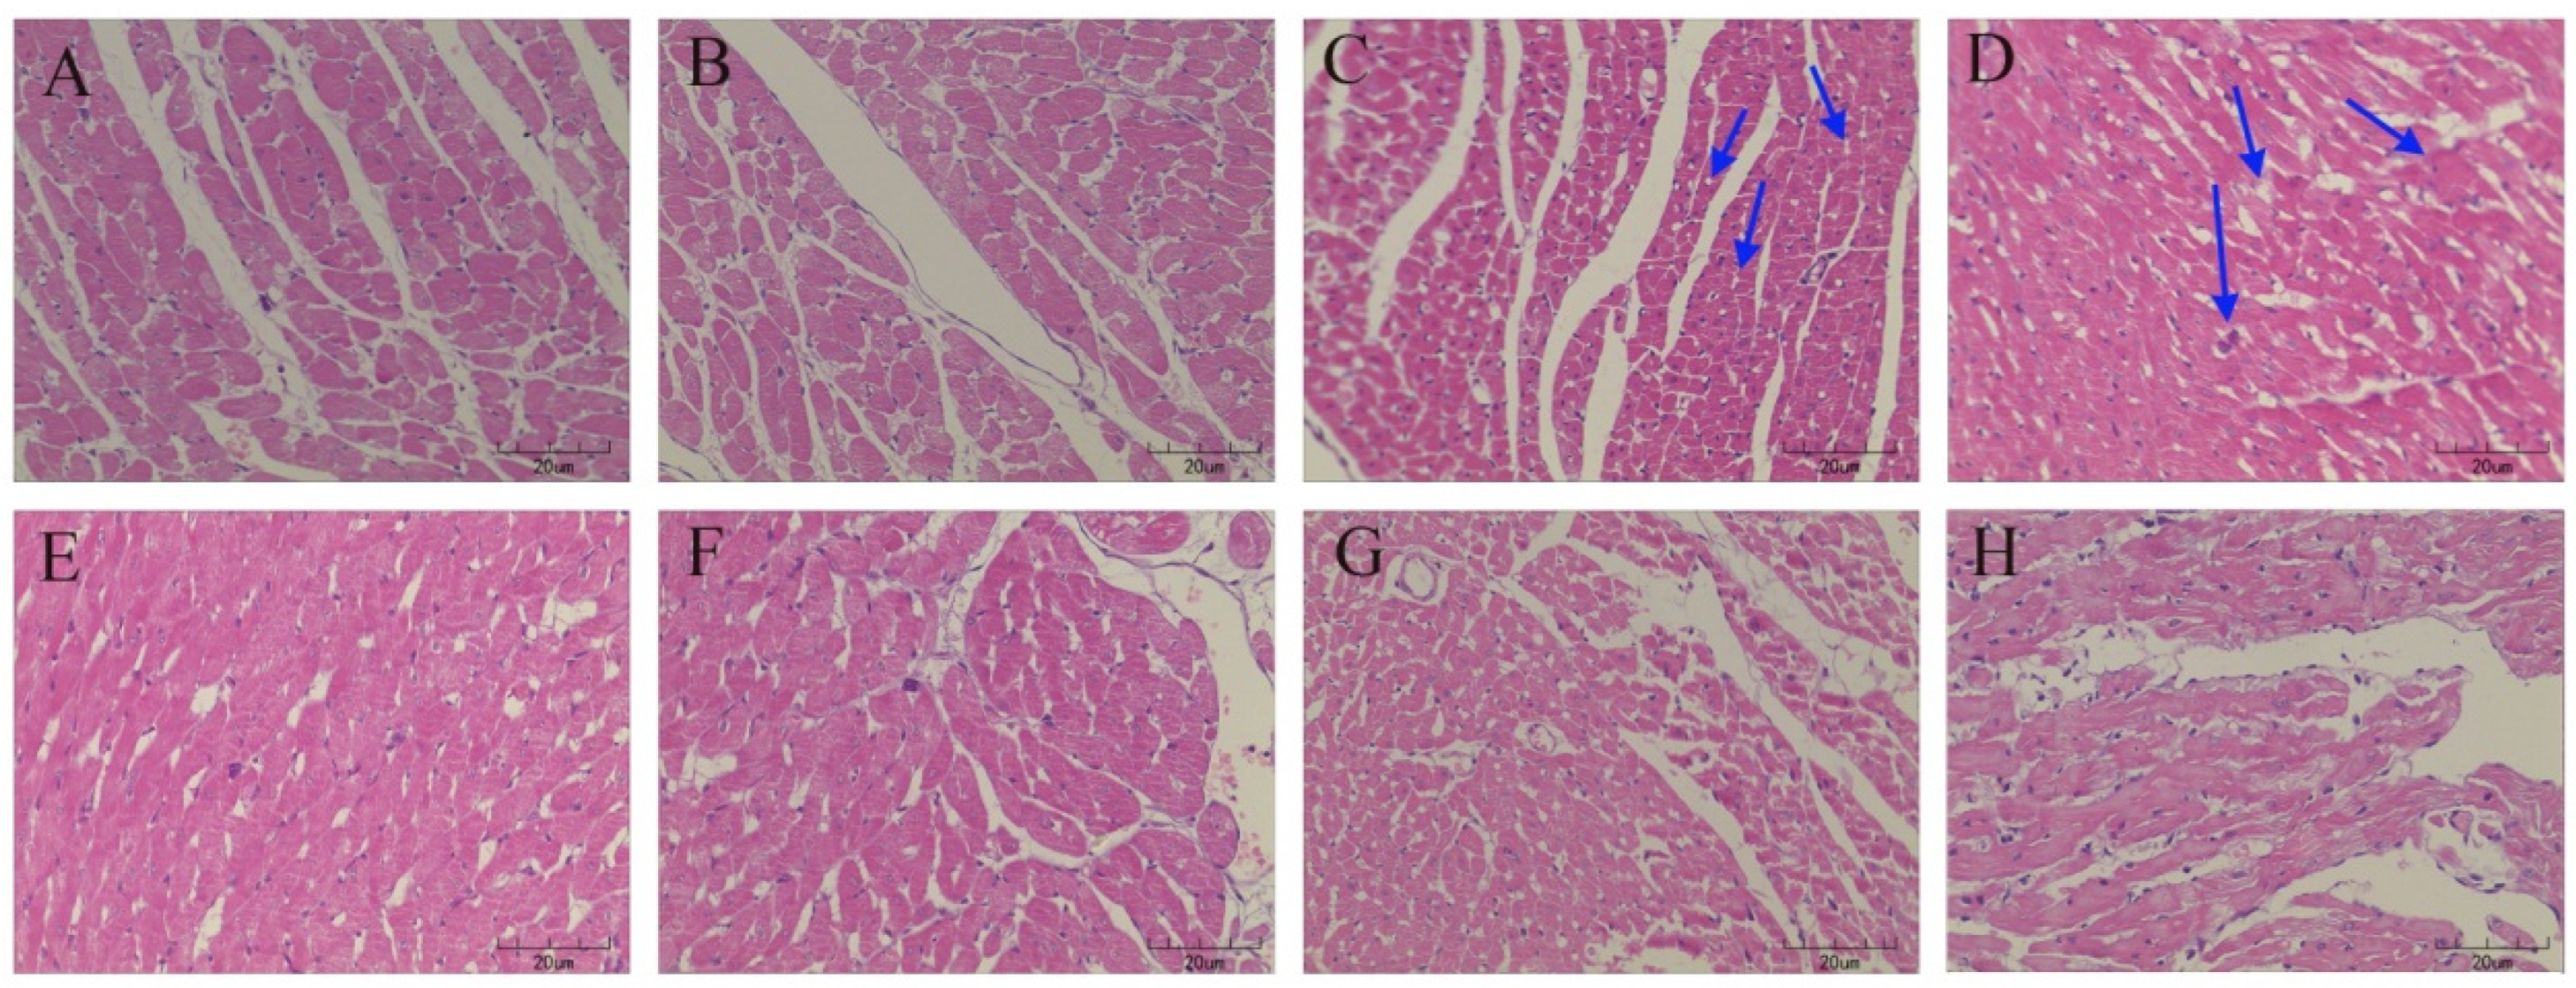

3.1. GDL Protect against CuSO4-Induced Heart Injury in Rats

3.2. Effect of GDL on Ultrastructural Changes in the Heart Tissue